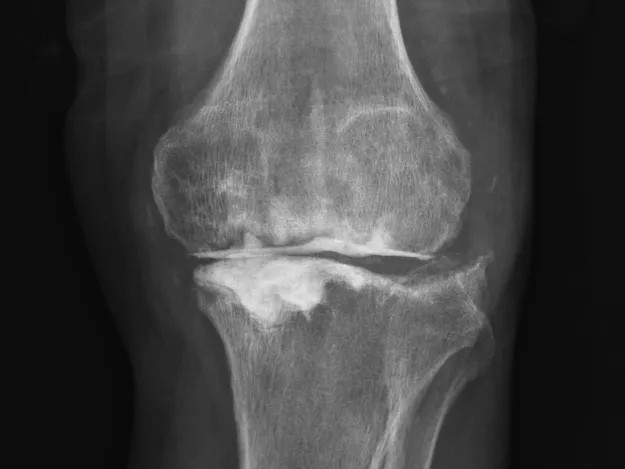

68歲的張先生(化名),本以為一次膝關(guān)節(jié)單髁置換手術(shù)能終結(jié)他的疼痛。然而,術(shù)后感染不期而至,將他的生活拖入長(zhǎng)達(dá)8個(gè)月的灰暗期。

膝關(guān)節(jié)持續(xù)紅腫、疼痛,每一步都伴隨著不適與恐懼。反復(fù)治療,效果卻不盡如人意。傳統(tǒng)手段面對(duì)此類術(shù)后感染、結(jié)構(gòu)遭破壞的復(fù)雜局面,往往力不從心,患者可能需要經(jīng)歷多次手術(shù),且功能恢復(fù)難以保障。

清創(chuàng)只是第一步,如何在一片“復(fù)雜地形”中重建一個(gè)穩(wěn)定、功能良好的膝關(guān)節(jié),是更大的挑戰(zhàn)。為此,團(tuán)隊(duì)引入了計(jì)算機(jī)輔助手術(shù)規(guī)劃系統(tǒng)。

通過患者的CT數(shù)據(jù),系統(tǒng)構(gòu)建出膝關(guān)節(jié)的三維數(shù)字模型,精確評(píng)估骨缺損的范圍與形態(tài)。醫(yī)生可以在虛擬空間中,提前模擬手術(shù)過程,為患者“量體裁衣”,規(guī)劃出假體安放的最佳位置、角度以及所需填充骨缺損的特殊墊塊型號(hào)。